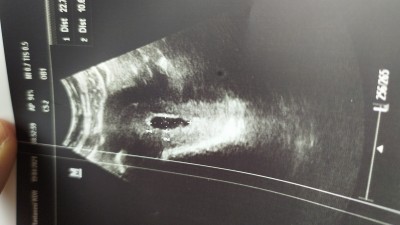

image

boyle bir durum yaşayıp düşük yapar var mı ya da yapmayan çok tedirginim

Gebelik haftası 7+3

Ben sabah gitmiştim aşağı doğruydu kese doktor düşük olabilir dedi sonra öğleden sonra gittim kese normla.dedj ama sağlıksız gebelik gibi duruyo dedi. Bende de kanama var ama ultrasonda görünmedi sanırım adet görüyorum

Düşük olacak diye sürekli düşünüp kendini üzme. Bu şekilde keseye sahip olan çok kadın var. İnternetten araştır. Fasulye gibi uzun kesenin olması hemen düşük olacağı anlamına gelmiyor. Önemli olan sınırlar. Sınırlarda bozulma yoksa bu çok sorun olacak birşey değil. Bol bol su iç

Kanaman varsa biraz durum değişir tabi düşük tehlikesi olabilir. Kanaman olmasaydı kese şekli zamanla düzeliyor çünkü.